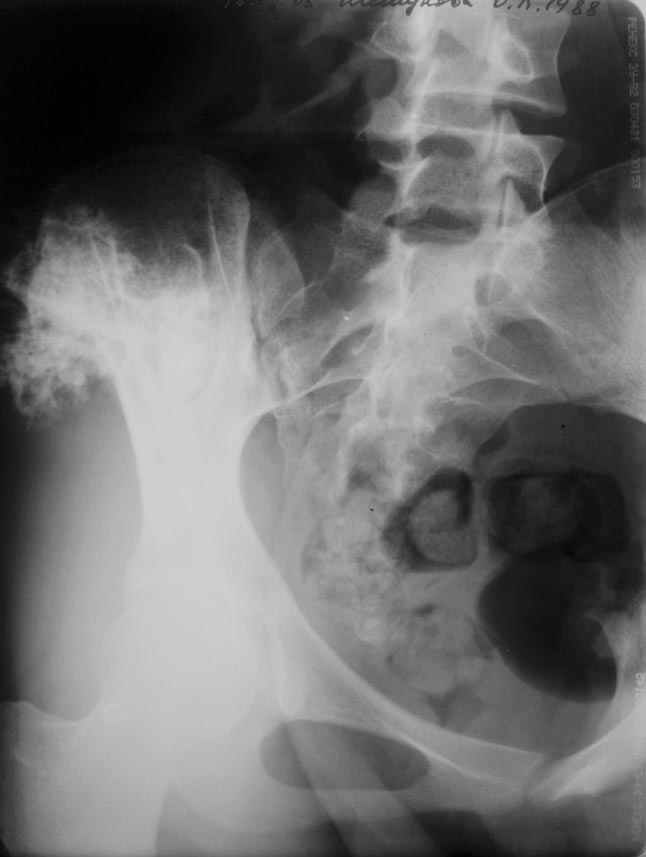

Остеохондрома подвздошной кости